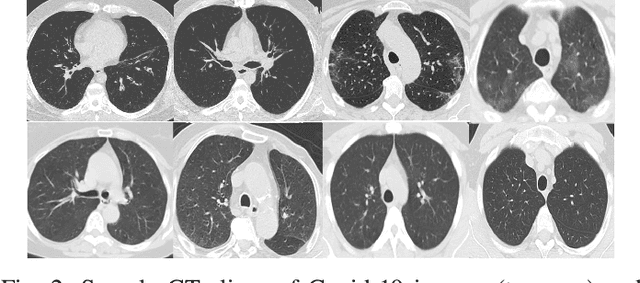

Deep learning is effective in diagnosing COVID-19 and requires a large amount of data to be effectively trained. Due to data and privacy regulations, hospitals generally have no access to data from other hospitals. Federated learning (FL) has been used to solve this problem, where it utilizes a distributed setting to train models in hospitals in a privacy-preserving manner. Deploying FL is not always feasible as it requires high computation and network communication resources. This paper evaluates five FL algorithms' performance and resource efficiency for Covid-19 detection. A decentralized setting with CNN networks is set up, and the performance of FL algorithms is compared with a centralized environment. We examined the algorithms with varying numbers of participants, federated rounds, and selection algorithms. Our results show that cyclic weight transfer can have better overall performance, and results are better with fewer participating hospitals. Our results demonstrate good performance for detecting COVID-19 patients and might be useful in deploying FL algorithms for covid-19 detection and medical image analysis in general.